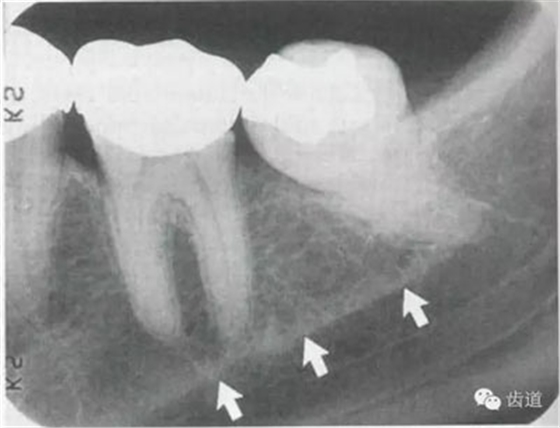

4)外斜線:

由升支前緣下部斜向前下方,為一密度高的帶狀影像。常重疊在第二、三磨牙牙冠處、頸部或根部,使牙髓室或根管不能清晰顯示

5)下頜管:

位于磨牙牙根尖下方,呈寬約為0.4cm凹面向下邊緣整齊的帶狀密度低的影像,其兩側(cè)有密度高的線條狀影像,為下頜管骨密質(zhì)